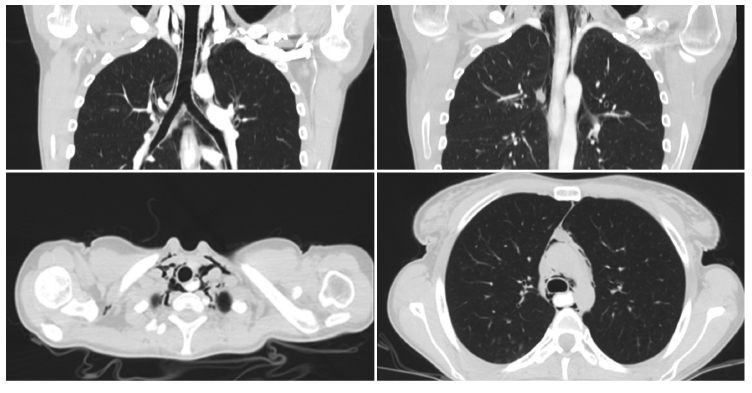

Se decide realizar un estudio dirigido mediante una TCMD de tórax, de abdomen y pelvis, con contraste oral y endovenoso, en la que se reconoce un neumomediastino que se extiende desde la región supraclavicular bilateral hasta el mediastino posterior y anterior (Figura 1).